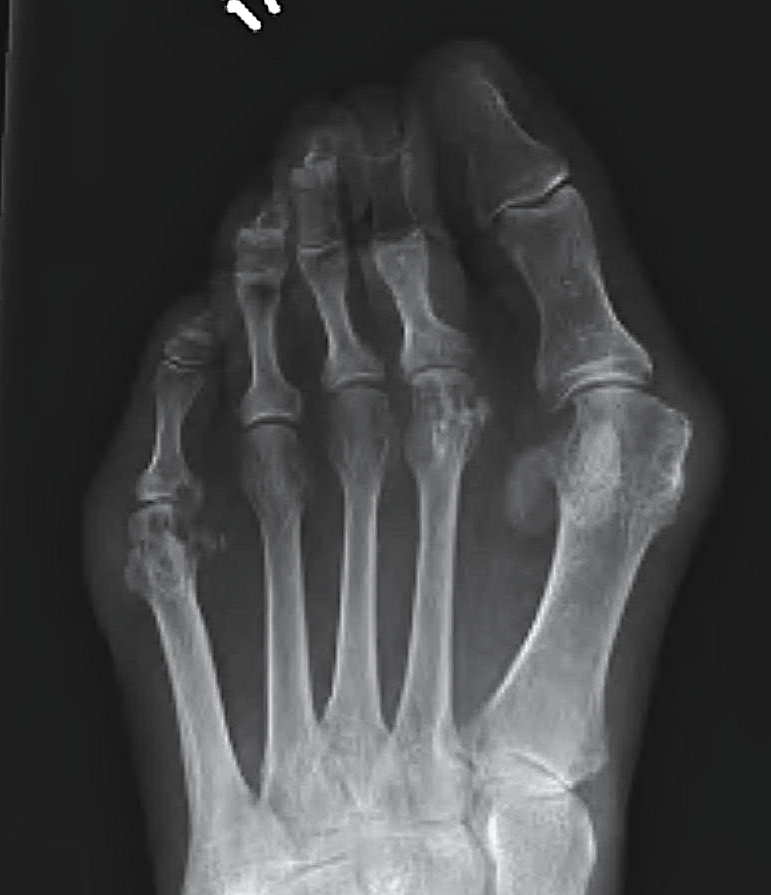

Muller-Weiss disease

Definition

Spontaneous osteonecrosis of the navicular